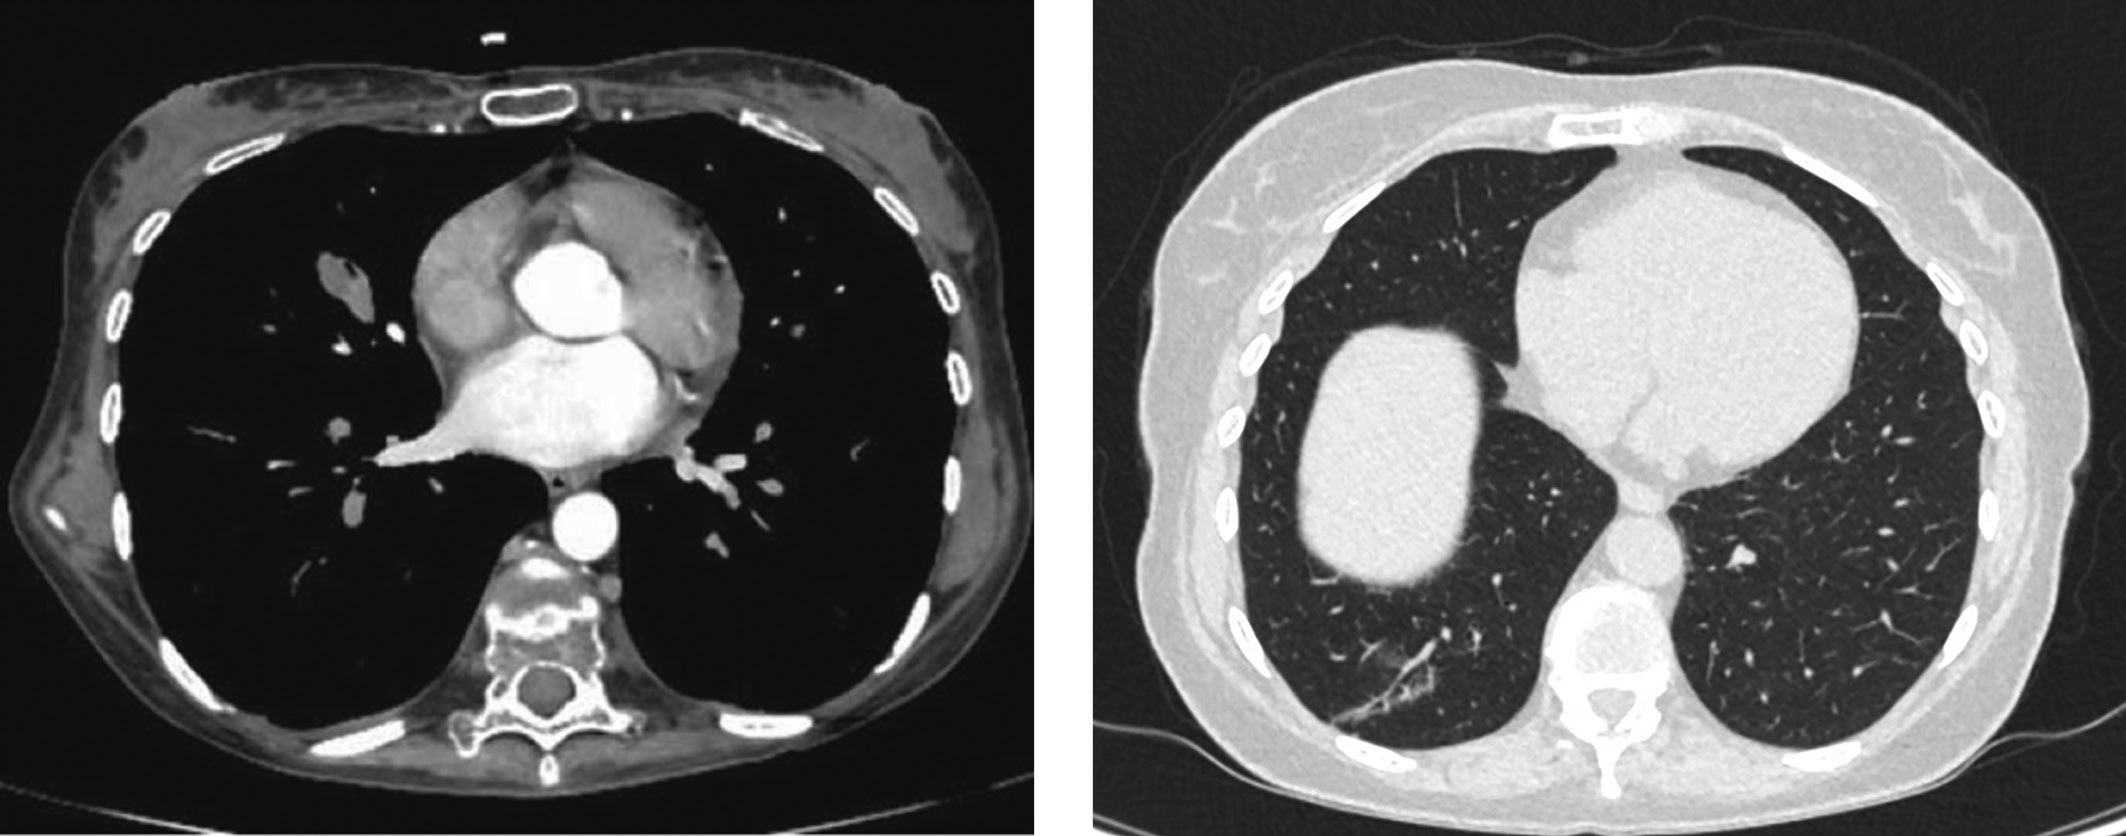

1. Рисунок 1. МСКТ органов грудной клетки пациентки К. с контрастным усилением. | |

РЕЗУЛЬТАТЫ. Возраст больных варьировал от 18 до 72 лет (36±15). По данным мультиспиральной компьютерной томографии органов грудной клетки были выявлены образования в легких размерами от 5 до 25 мм. Пациентам, набравшим от 18 до 23 баллов, из-за тяжести состояния проводили резекцию легкого. При сумме баллов от 14 до 18 выполняли сегментэктомию с лимфодиссекцией. При сумме баллов меньше 14 проводили лобэктомию с лимфодиссекцией. При плановом гистологическом исследовании у всех больных подтверждена НЭО легкого различной степени дифференцировки. Результаты лечения пациентов прослежены в период от 6 до 60 мес, с медианой 19 мес [10; 24]. Регресс клинических проявлений гиперкортицизма через 1 год динамического наблюдения выявлен у 83% больных. Спустя 60 мес наблюдения 10 пациентов (71,4%) имели стойкий клинический эффект после проведенного хирургического лечения с полным регрессом симптомов гиперкортицизма.